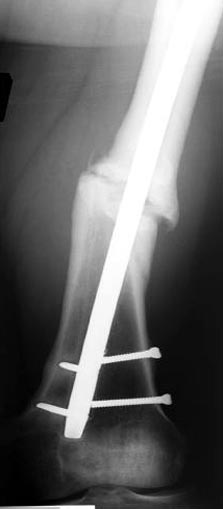

Снимки представлены: 1 мес; 3 мес; 1 год; 2 года, предоперационные и ротационная КТ грамма

Деформация:

Вальгус- 17 градусов

Рекурватум 5 градусов

Укорочение 2.5см

Ротационно 22 градусов внутренная

Смещение диафиза по поперечнику 75%

Операцию провели в два этапа, сперва удалили штифт, рассверливание римером на пару мм большего диаметра, определение чувствительности на анаэробную и аэробную культуру (где исследования показали негативный результат чувствительности), через дней десять - начали аппаратную фиксацию.